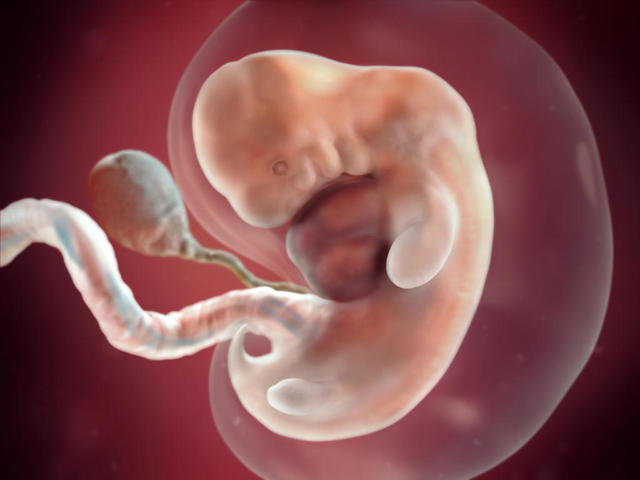

Se desarrolla lo que denominamos embrión, que tiene, básicamente, una cabeza, un tronco y una cola rizada.

Esta semana de embarazo está marcada por:

- La sujeción del blastocisto en el útero, ya que va a ser su “casa” durante todo el embarazo.

- La creación del saco o cavidad amniótica incluido el líquido amniótico..

- La cavidad coriónica, donde estará fijado el embrión sobre un pedículo de fijación, que se transformará en el cordón umbilical.